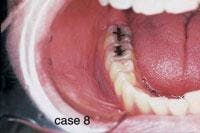

CASE 8

Smokeless tobacco keratosis

1. Where is the smokeless tobacco keratosis likely to occur?

a. mucobuccal fold area

b. dorsal tongue

c. hard palate

d. gingiva

2. What is the clinical appearance of the smokeless tobacco keratosis?

a. white color

b. raised or flat contours

c. smooth, granular or corrugated

d. any of the above

3. What is the recommended treatment for the smokeless tobacco keratosis?

a. surgical removal

b. radiation therapy

c. discontinue use of product

d. none of the above